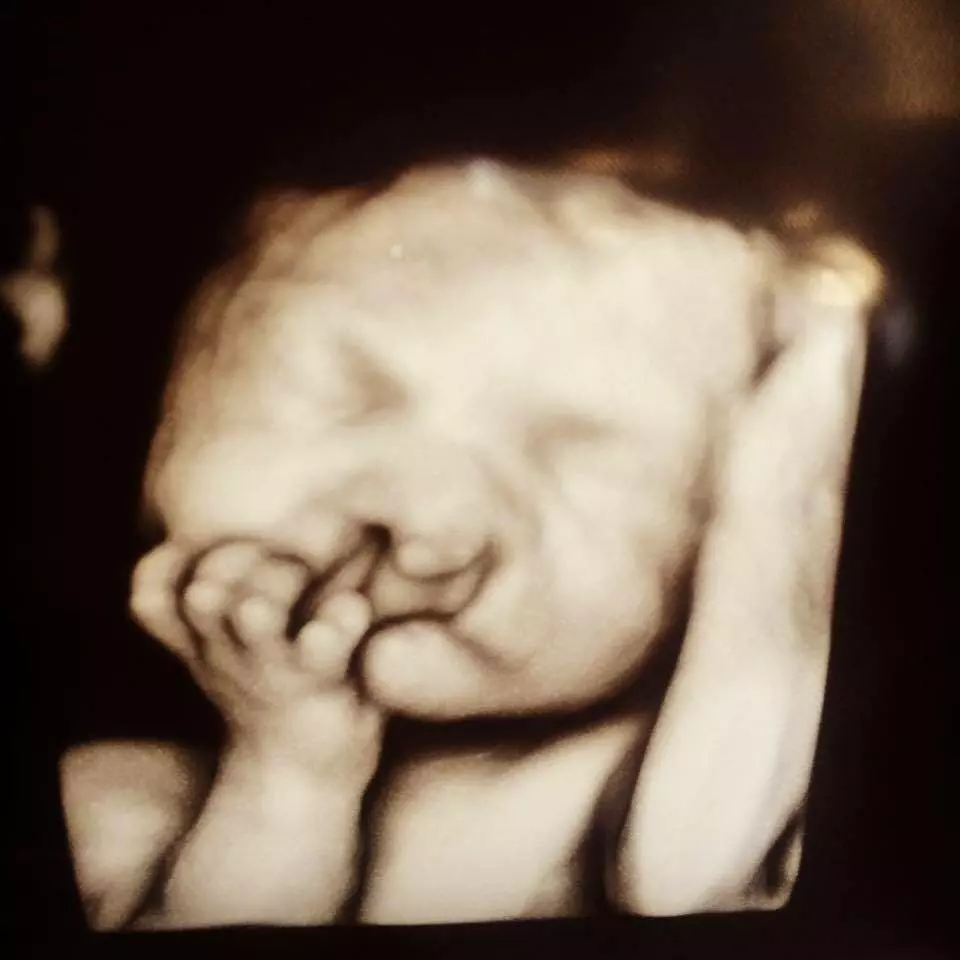

Lors de chaque naissance, un sentiment de joie indescriptible envahit les parents. Soucieux du bien-être de leur bébé, ces derniers ne poussent leur premier soupir de soulagement qu’après avoir reçu la confirmation du médecin concernant un bon état de santé de leur enfant. Pour ce couple, les choses ne se déroulent pas tout à fait comme prévu. En effet, à 24 semaines de grossesse, ils apprennent que leur enfant sera porteur de fentes labio-palatines.

Selon la SFODF (Société Française d’Orthopédie Dento-Faciale), les fentes labio-palatines sont des malformations qui ne touchent qu’un bébé sur 750. Celles-ci se caractérisent par un « déficit tissulaire, squelettique et dentaire » qui peut toucher différentes zones du visage de manière séparée ou groupée. En effet, cette condition assez rare peut se produire sous plusieurs formes : « partielle ou totale, unilatérale (droite ou gauche) ou bilatérale ».

Nécessitant une intervention chirurgicale pluridisciplinaire pour être traitées, les fentes labio-palatines entraînent de nombreux troubles de « la nutrition, la respiration, l’audition, la parole et la croissance ». Comme l’explique la SFODF, les effets varient en fonction de l’emplacement et de l’ampleur de la fente. En effet, celle-ci résulte d’unefusion incomplète des bourgeons de la face chez le fœtus, menant ainsi à une malformation du visage du nouveau-né.

Atteint d’une fente labio-palatine bilatérale, Brody, âgé de quelques mois à peine, subit l’insertion d’une sonde de gastrostomie (SGS) afin d’assurer son alimentation. En effet, les complications de sa malformation sont nombreuses et nécessitent des opérations chirurgicales multiples très coûteuses.